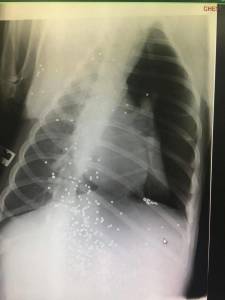

Il-każ ta’ moħqrija tal-annimali seħħ fl-għelieqi ta’ madwar il-Magħtab, f’żona magħrufa bħala Ta’ Żwejt u frekwentata mill-kaċċaturi, qrib l-istalel taż-żwiemel li għandha sidtu. Malli sarlu l-X Ray kien evidenti li xi ħadd spara tiri ta’ senter lejn il-kelb, tant li f’ġismu nstabu għexieren ta’ ċomb.